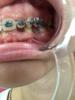

3.... фото не для слабонервных

В общем ВЧ месяц и в субботу поставили мне на НЧ, вчера так все болело, что не было сил писать.

Меня отфоткали и прикладываю еще фотки для сравнения, где БС неделька.

Еще у меня крутой аксесс в виде съемной пластины с зубами) дикция в ней ужасная, мне она максимально сильно не нравится.

зубы дракона да минимум три импланта пока планируется..

aav с костной тканью конечно же все не так хорошо, но будут пересаживать. Это вопрос, который будет обсуждаться через годик, а пока надо на место поставить то, что есть.